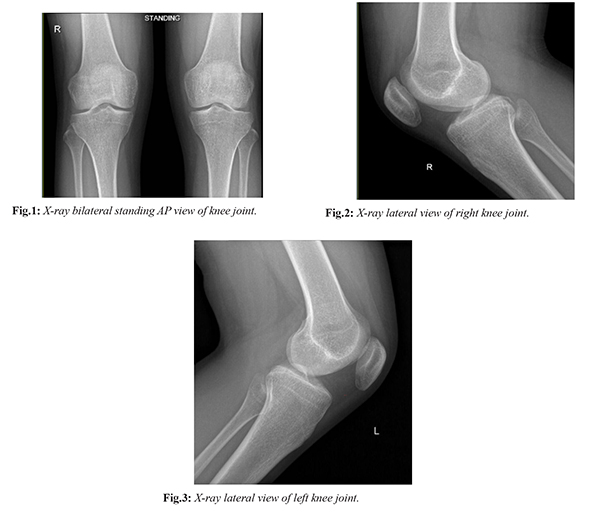

H. A. A., a 24-year-old previously healthy athletic female, presented to our clinic with a 6-month history of bilateral knee pain localized to the anterolateral aspect of both knees. The pain was exacerbated by activities such as squatting, climbing stairs, and walking downstairs. She also reported stiffness and swelling in both knees, particularly after periods of inactivity. She had no history of trauma or previous knee surgery. Physical examination revealed tenderness to palpation over the patellar tendon and patellofemoral joint lines. Range of motion was intact. The patient's quadriceps strength was found to be weak, particularly in the vastus medialis obliquus (VMO) muscle, patellar mal-tracking was noticed in both knees, more on the right side, and both hamstrings were tight. Standing AP [Fig.1], and lateral [Fig.2,3] X-ray views of the knee joints showed that the articular surfaces appear normal with no presence of peri-articular pathology, normal width of joint spaces, no evidence of patellar subluxation, no lucent fracture lines, and no abnormal soft tissue shadows.